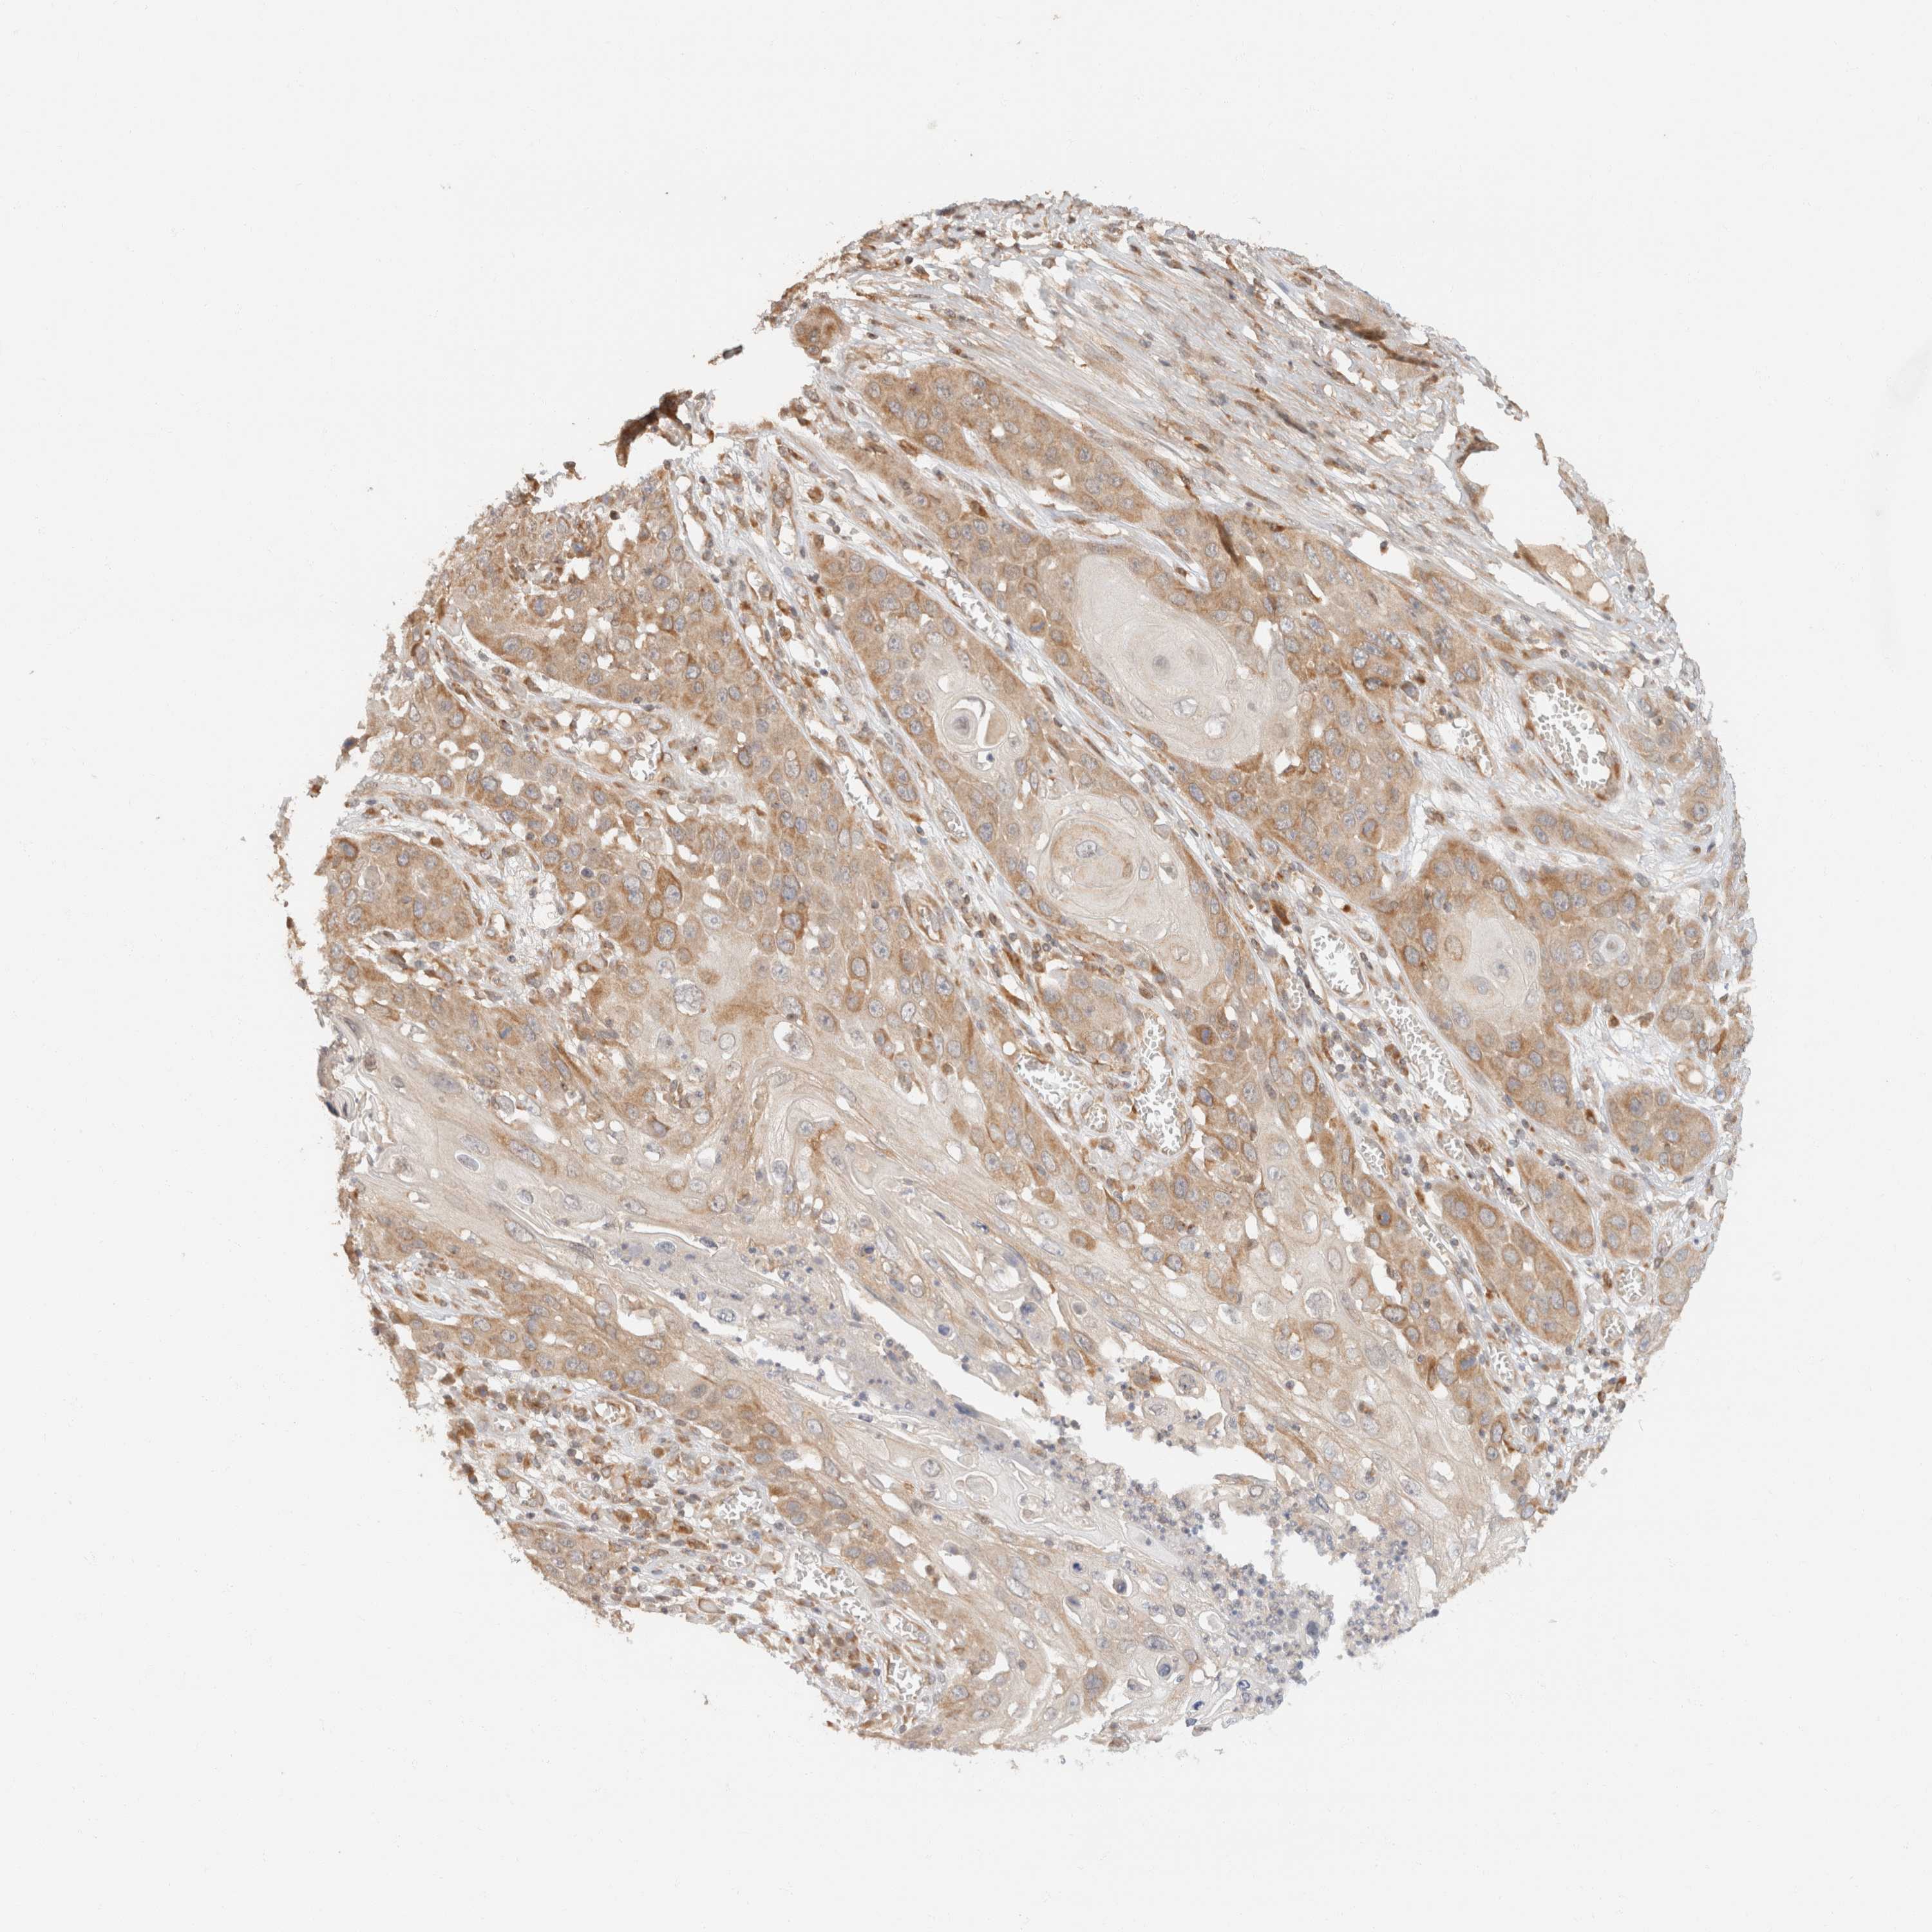

SKIN CANCER - Protein expressioni

A mouse-over function shows sample information and annotation data. Click on an image to view it in a full screen mode. Samples can be filtered based on level of antibody staining by selecting one or several of the following categories: high, medium, low and not detected. The assay and annotation is described here.

Antibody stainingi

Antibody staining in the annotated cell types in the current human tissue is reported as not detected, low, medium, or high, based on conventional immunohistochemistry profiling in selected tissues. This score is based on the combination of the staining intensity and fraction of stained cells.

Each image is clickable and will lead to virtual microscopy that enables deeper exploration of all samples and also displays staining intensity scores, fraction scores and subcellular localization as well as patient and tissue information for each sample.

Antibody CAB017041

Squamous cell carcinoma, metastatic, NOS

Squamous cell carcinoma, NOS